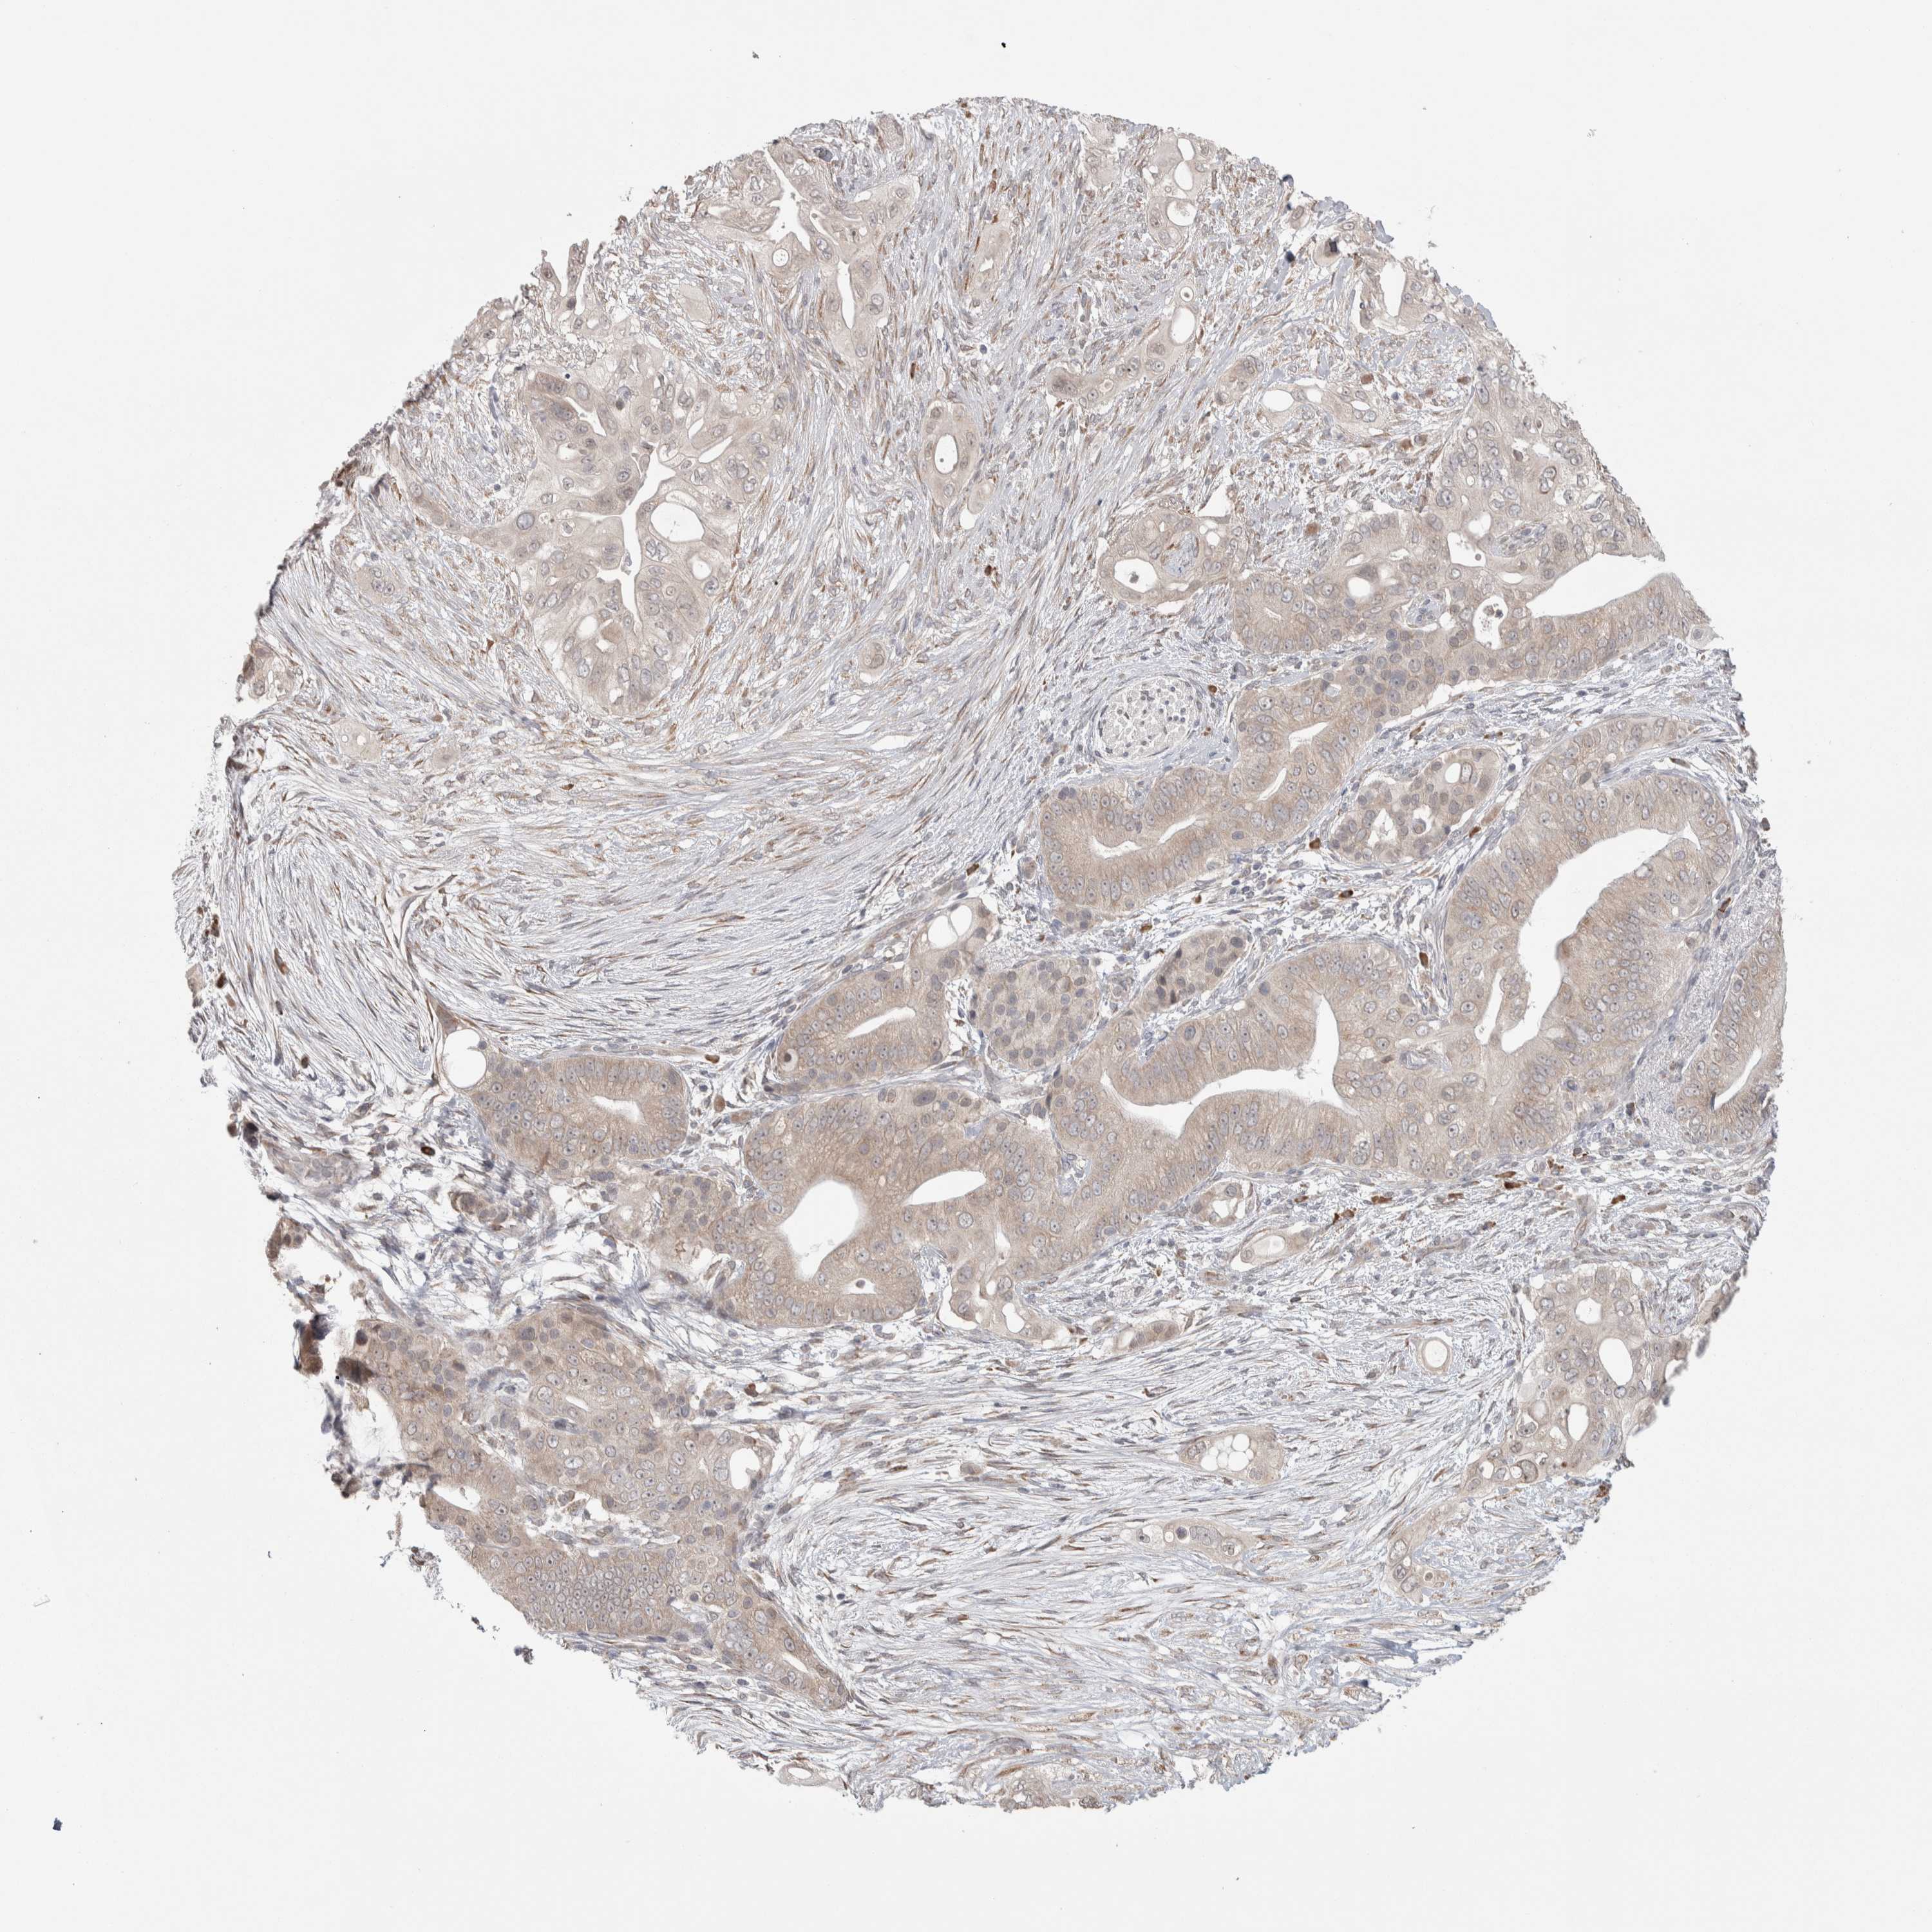

PANCREATIC CANCER - Protein expressioni

A mouse-over function shows sample information and annotation data. Click on an image to view it in a full screen mode. Samples can be filtered based on level of antibody staining by selecting one or several of the following categories: high, medium, low and not detected. The assay and annotation is described here.

Note that samples used for immunohistochemistry by the Human Protein Atlas do not correspond to samples in the TCGA dataset.

Antibody stainingi

Antibody staining in the annotated cell types in the current human tissue is reported as not detected, low, medium, or high, based on conventional immunohistochemistry profiling in selected tissues. This score is based on the combination of the staining intensity and fraction of stained cells.

Each image is clickable and will lead to virtual microscopy that enables deeper exploration of all samples and also displays staining intensity scores, fraction scores and subcellular localization as well as patient and tissue information for each sample.

Antibody HPA024578

Antibody CAB002677

Staining

High

Medium

Low

Not detected

Intensity

Strong

Moderate

Weak

Negative

Quantity

>75%

75%-25%

<25%

None

Location

Nuclear

Cytoplasmic/membranous

Cytoplasmic/membranous,nuclear

Adenocarcinoma, NOS